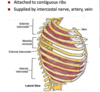

External, Internal, and innermost intercostals

origin, insertion, innervation, actions

External-forced inspiration,

Internal- forced expiration,

Innermost- deepest, elevates ribs

Ext & Innermost don’t go all the way to sternum, Internal does. None go all the way to vertebrae